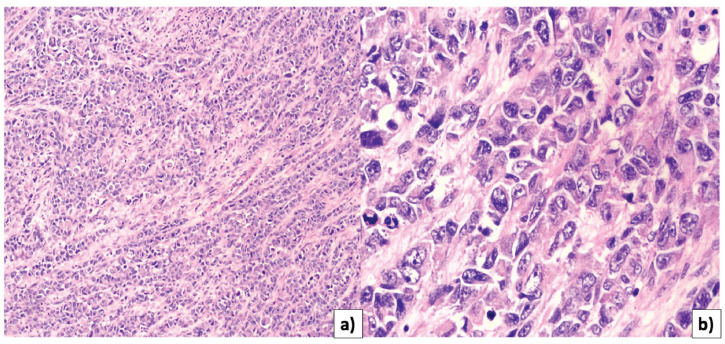

Material and methods: A 76-year-old patient who presented to the national cancer referral center in Bogota (Colombia), where she was diagnosed with a uterine collision tumor consisting of a seroustype endometrial adenocarcinoma and a cervical adenosarcoma. The patient underwent surgical treatment followed by chemotherapy and supplemental radiotherapy, and died 16 months later. A search was conducted in the Medline via PubMed and Embase databases, including reports and case series of women with a diagnosis of uterine collision tumor, with retrieval of information regarding diagnosis, treatment and prognosis. A narrative summary of the findings was made.